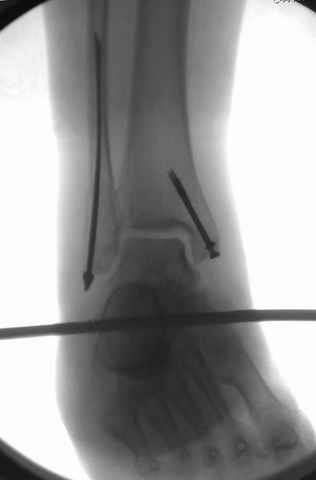

На снимках варианты фиксации малоберцовой:

№ 2-5 при огнестрельном переломе

№ 6-11 при pilon percutaneus fixation